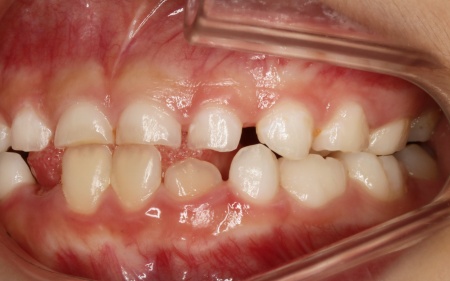

9歳女の子 反対咬合を顎の成長を利用した矯正装置を用いて改善した症例

治療前

診断結果 拝見したところ、患者様は乳歯のみが生えている乳歯列期の段階でしたが、この時点ですでに反対咬合が認められました。

反対咬合とは、下の前歯が上の前歯よりも前に出ている状態のことで、一般的に「受け口」とも呼ばれます。

反対咬合は、このまま放置すると永久歯に生えかわったあとも継続してしまうおそれがあり、顎の成長や噛み合わせ、発音や顔貌にも悪影響を及ぼすことがあります。

しかし、この時期は顎の骨が成長段階にあり、適切な治療を行うことで改善が期待できるため、早期に治療を開始する必要があると診断しました。